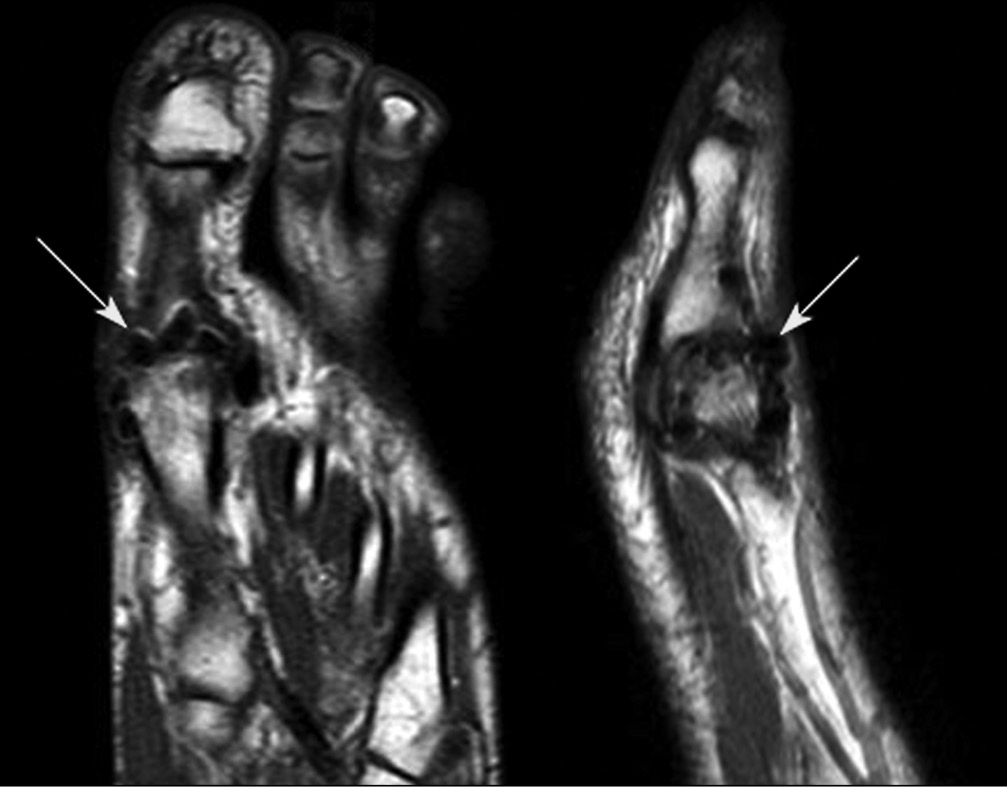

Особый интерес представляет собой картина магнитно-резонансной томографии стопы после операции. В области оперированной головки I ПК определяются гроздевидные образования — «артефакты», трактовка природы которых затруднена (рис. 13).

Рис. 13. Магнитно-резонансная томография стопы через 12 мес. после операции (пациентка Д., 40 лет)

Также стоит отметить, что артефакты в I ПФС, обнаруженные на магнитно-резонансной томографии, ранее не были описаны в литературе, поэтому невозможно дать их точную интерпретацию.